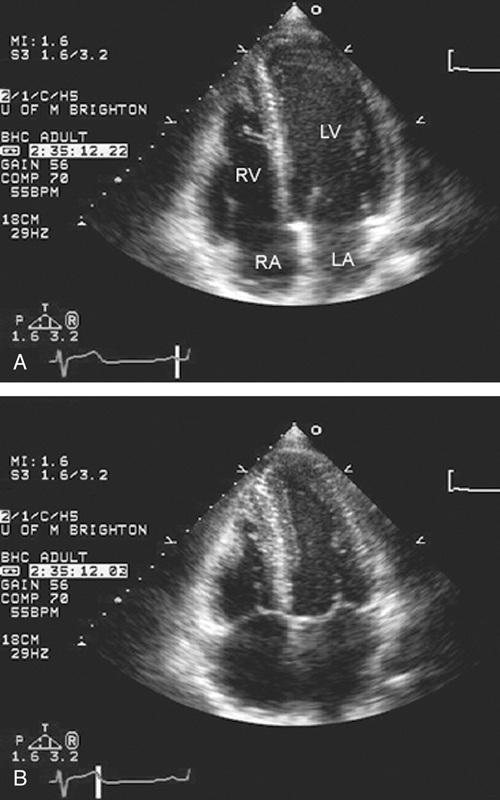

فحوصات تشخيصية لبعض امراض القلب والشرايين التاجية